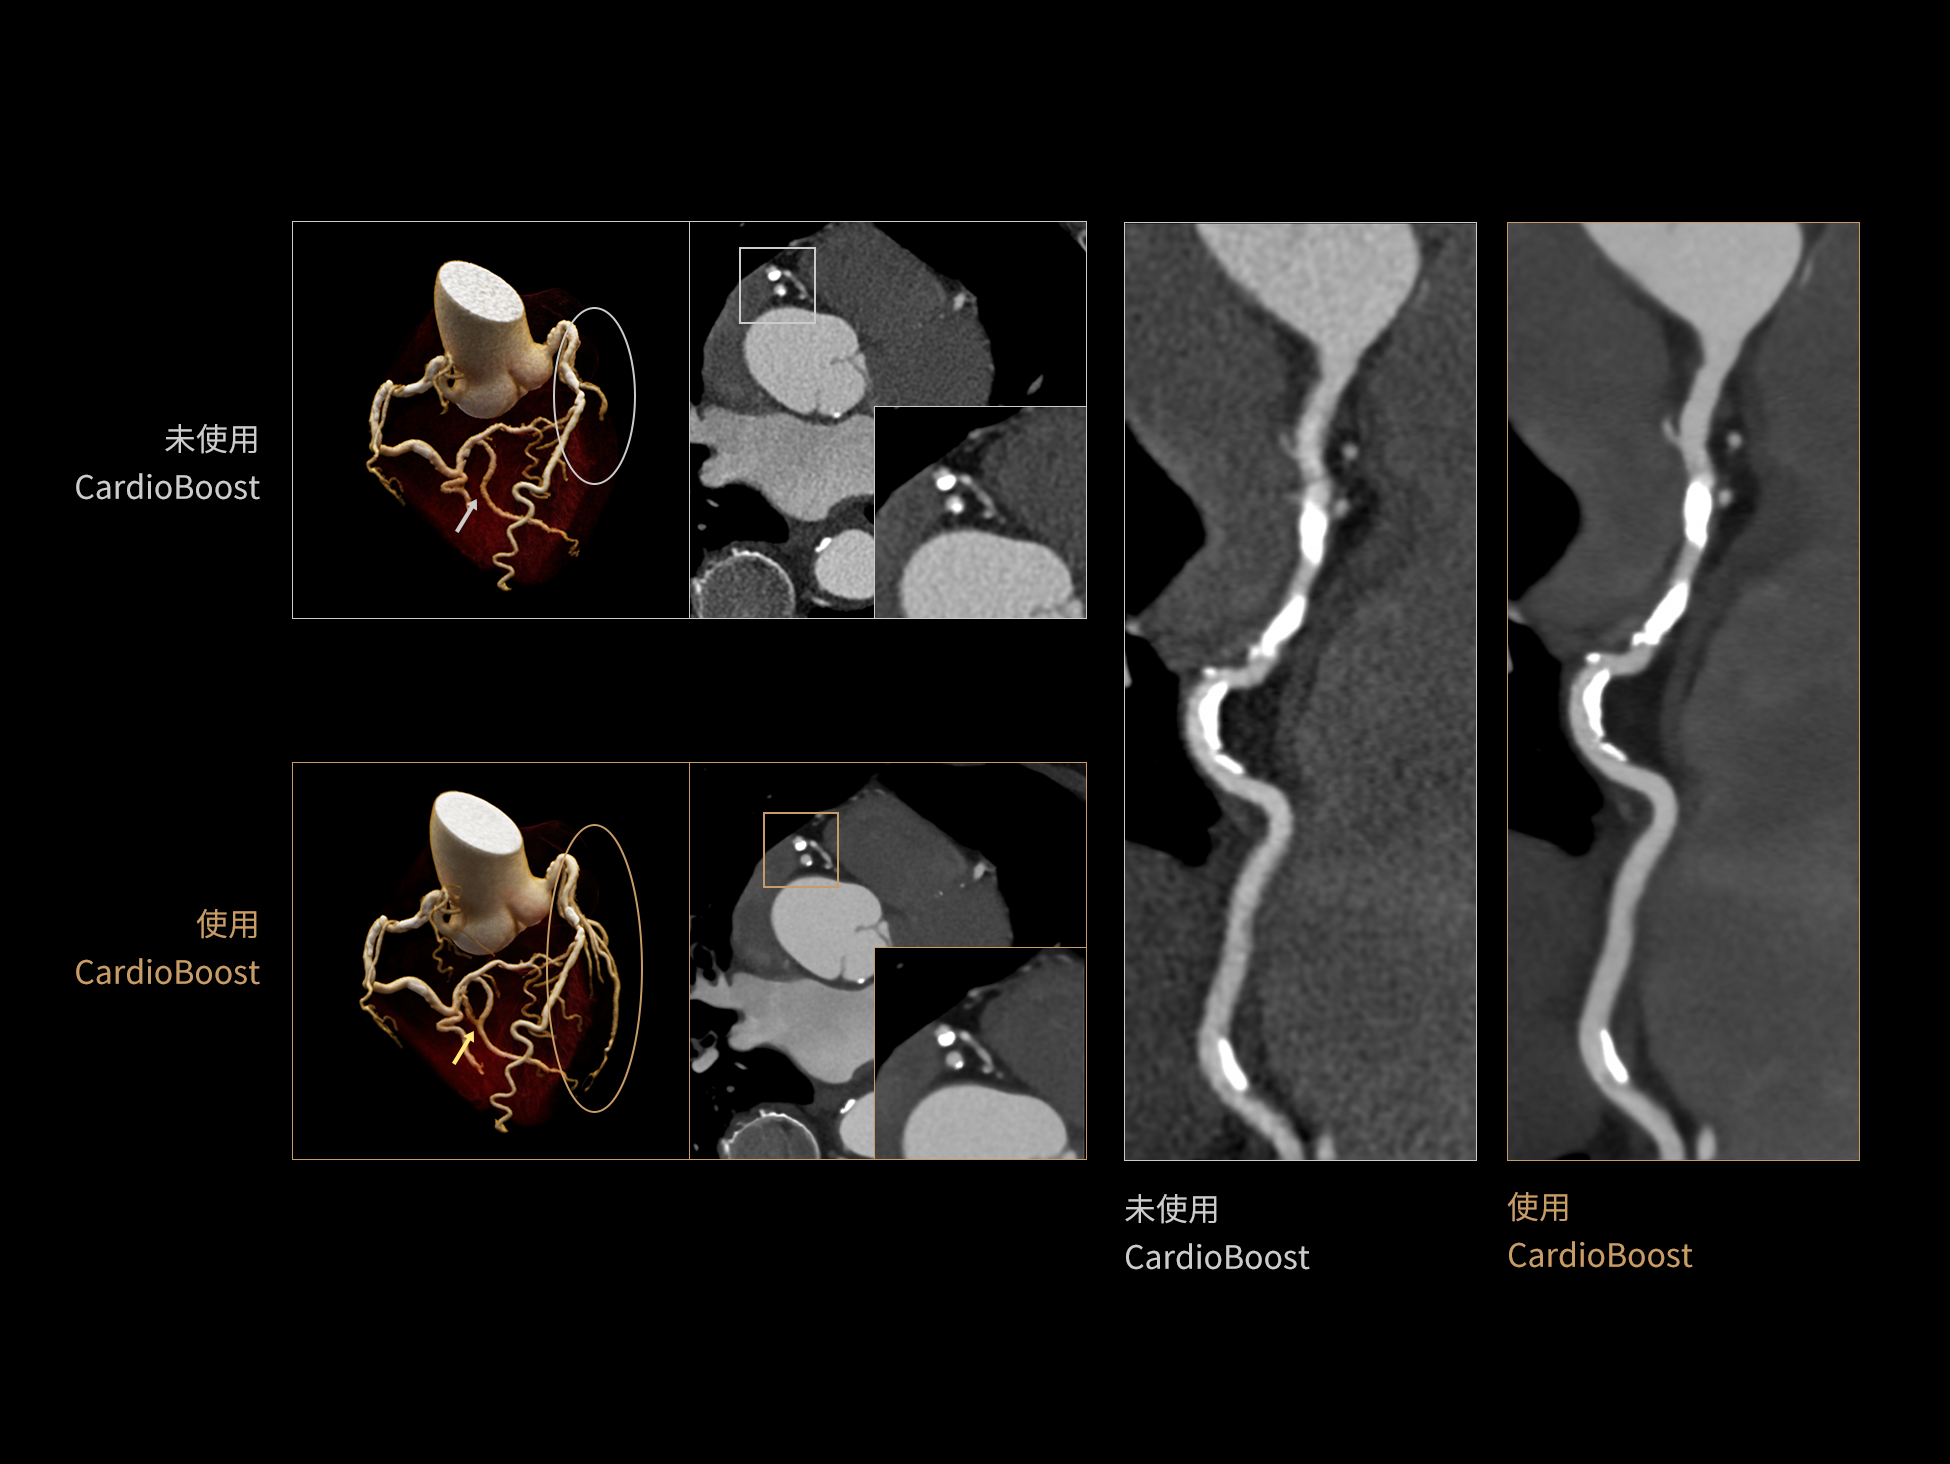

CardioBoost:专属网络设计,重塑心脏影像表现

目前心脏的 CT 检查还存在辐射剂量偏高、空间分辨率不足、 致密钙化伪影影响冠脉狭窄程度评估等方面的限 制[1][2]。CardioBoost 技术专为心脏 CT 高清成像而开发,通过 3D 神经网络的深度学习技术,利用先进的注意力机制在识别关键成像特征方面的出色表现,能够精确地聚焦于斑块、支架以及微小血管等关键细节,清晰展示这些结构与冠脉血管的边界,从而显著提高诊断的准确性,并提升医生的诊断信心。创新的 CardioBoost 心脏图像重建算法,不仅实现了图像清晰度的提升和伪影的去除,更能在减少辐射剂量的同时,保证心脏图像的高质量和图像纹理的自然。

采用 3D 神经网络的空间结构优势与精细的组织分类能力,CardioBoost 技术优化了组织对比,高清展示血管斑块,使斑块与血管边缘的轮廓清晰可辨,提升斑块诊断与评估的精确性。

借助 3D 神经网络设计、空间注意力机制聚焦与特征强化作用,CardioBoost技术提升图像的空间分辨率,实现冠脉支架的高清成像,对支架形态与管腔通畅度的评估更精准。

CardioBoost 整合先进的 3D 神经网络和空间注意力机制,大幅增强数据处理的速度与精确度。该技术能有效抑制由致密钙化引起的晕状伪影,清晰展现钙化斑块的原始结构和大小,对冠脉狭窄的评估更加精确可靠。